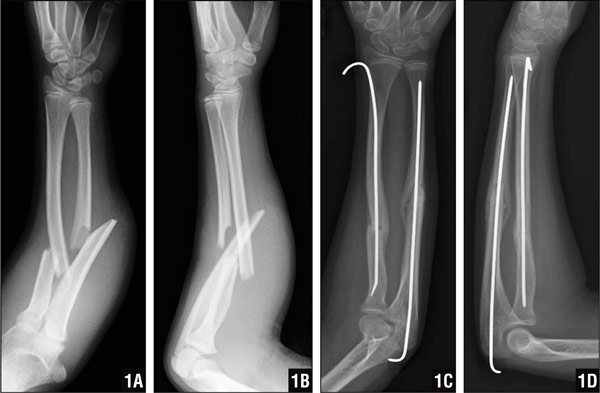

Диагностика

Закрытый перелом руки имеет много сходства с другими вариантами травмы, такими как сильных вывих, ушиб и другие. Именно поэтому, чтобы точно определить, что произошел перелом, врачи проводят нужную диагностику. Самым верным способом в данном случае будет проведение рентгенографии, которая позволит определить не только наличие перелома, но и его точную локализацию, позволяющую подобрать подходящее лечение.

Если рентгенография дает сомнительные и размазанные данные, врачи могут принять решение назначить дополнительное исследование с помощью компьютерной томографии. Она уже даст точную картину происходящему, определит не только наличие поврежденных костей, но еще и сосудов, мягких тканей и даже нервных окончаний. Только точные методы диагностики позволят определить наличие и характер травмы.